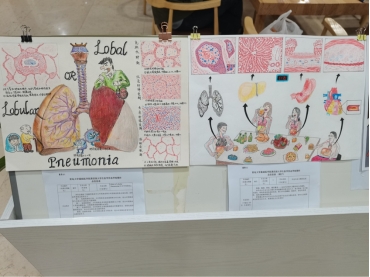

作品名:《Lobar or LobularPneumonia(大/小叶性肺炎)》

作者:时新茹

指导老师:王宁

作品简介:本作品描绘了细菌性肺炎中大叶性肺炎和小叶性肺炎的各方面比较。本作品所表现出的有以下:第一、发病的部位不同,大叶性肺炎呈段或者肺大叶分布,而小叶性肺炎发生在肺小叶或在支气管周围;第二、发病的原因,大叶性肺炎多是肺炎链球菌1.2.3.7型,而小叶性肺炎大多混杂菌肺炎,主要是肺炎链球菌4.6.10型;第三、发病的性质,大叶性肺炎主要是肺泡腔内纤维素性炎,有特色的四期病程划分,而小叶性肺炎是化脓性肺炎;第四、发病的年龄,大叶性肺炎常见于青壮年,而小叶性肺炎多发生在幼儿或者老年人。

作品名:《不良生活习惯的危害》

作者:孟露露

指导老师:王宁

作品简介: 吸烟、酗酒、熬夜、暴饮暴食……这是当代绝大多数年轻人的通病。本作品以不良生活习惯对身体健康的危害为切入点,重点描述了其可能对消化、呼吸等系统造成的疾病:肺门中央型鳞癌、脂肪肝、消化性胃溃疡、冠状动脉粥样硬化等。希望通过本作品可以让人们认识到不良生活习惯的危害,呼吁人们要养成良好的生活方式,莫要透支自己的身体!